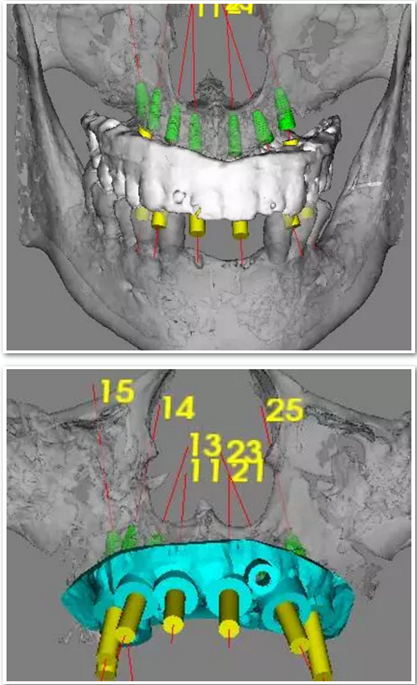

手術(shù)時(shí),帶上導(dǎo)板,逐級(jí)備孔,在15和25的位置需要進(jìn)行內(nèi)提升,因此對(duì)于備孔深度的把控尤為重要,導(dǎo)板的作用得到了重大發(fā)揮。

去掉導(dǎo)板,進(jìn)行上頜竇內(nèi)提升,填入骨粉,植入種植體。